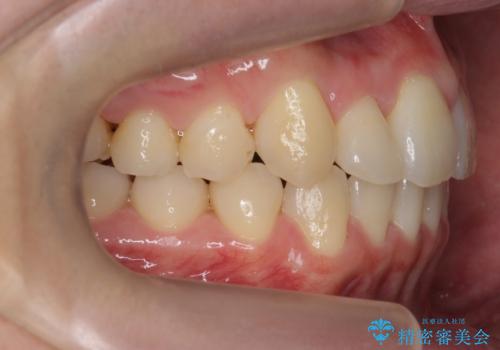

右上の奥歯を後ろに移動して、前に出すスペースを確保してから並べました。

前歯が内側に入っていると、笑った時にそこが黒くなり、歯が抜けたように見えます。

口を開けたとき、笑顔の印象が大きく変わり、大変喜んでいただけました。